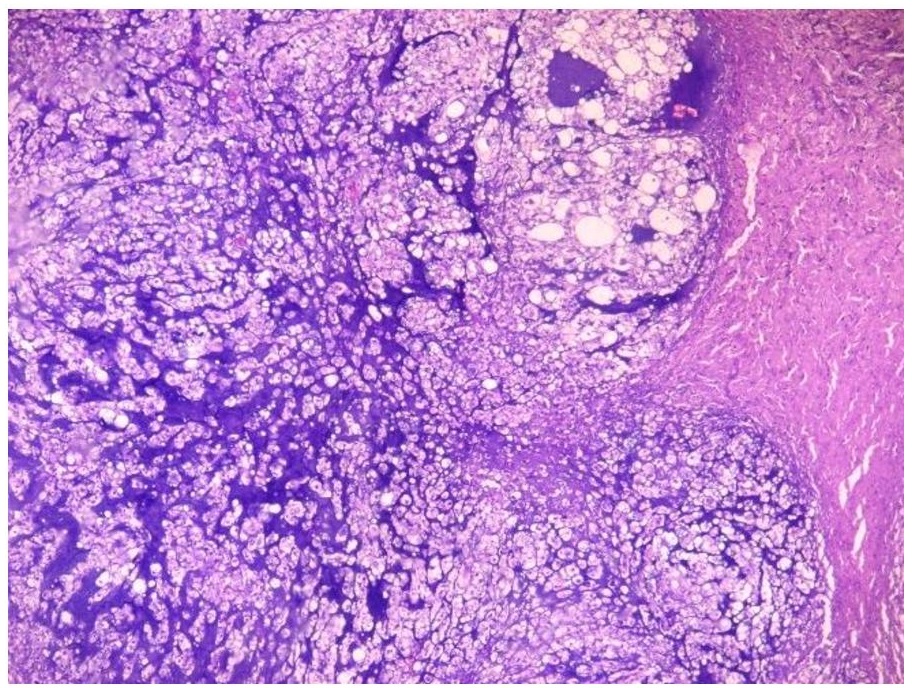

The primary mass measured 8 x 7.5 x 6 cm. The mass has cream-tan to tan, solid cut surfaces with foci of hemorrhage and necrosis. It is surrounded by a 0.2 cm-thick fibrous tissue. It is clearly-delineated from the surrounding muscle. Microscopic examination revealed the two (2) histologic components for the diagnosis of dedifferentiated chordoma. It consists of areas compatible with a conventional chordoma (Figures 1 and 2) and areas with sarcomatous differentiation (Figure 3). No transitional areas were seen between these components.

Figure 1. The tumor cells are infiltrative and are arranged in sheets, nests and chords. These areas are divided into lobules by fibrous septa (Hematoxylin and Eosin, 20x).

Figure 2. Cells with abundant pale, vacuolated/bubbly cytoplasm with small, hyperchromatic nuclei (physaliferous cells) seen alongside cartilage-like areas. There is mild to moderate nuclear atypia and rare mitoses (Hematoxylin and Eosin, 40x).